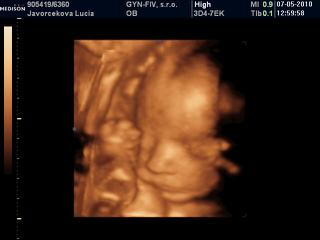

Lucy, nádherná je 😵

Bihan, dakujem 😵 ja som neobjektivna, pre mna je najkrajsia pod slnkom 😀

Lucy kraaaaaaaaaaaasna je 😵 😵 😵

A inak poloha je zadkom dole, hlavicka niekde v urovni pupka a nozky za hlavou a potom sa divim, ze mi kope hore 😀

Lucy, veď to je normálne, že pre teba bude vždy najkrajšia, ale má úplne objektívne nádherný malý nošte 😀

Lucy tiez si myslim, ze ma krasny maly nostek a to uuuuplne objektivne!